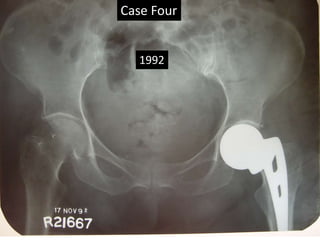

Case Four

1992

2000

2006

Case Three • Thisold man had AMP left hip before 1992 (X- rays) • He had fracture trochanter on right side – 2000. • DHS was done in 2000. • Last follow up 2006. • Rigid fixation by bone in fenestrations. • Medial migration of distal loose piece.